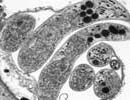

Cryptosporidium hominis IbA9G3 isolate 14-00278

Courtesy of Saul Tzipori, Tufts

| Comment: | Cryptosporidium hominis is the dominant species which infects humans. Although generally self-limiting, this disease can cause fatalities in children and immunocompromised adults. The genome sequence of Cryptosporidium hominis shows features consistent with its life cycle as an obligate parasite. This organism lacks the genes necessary for the production of a number of biochemical building block such as nucleotides and amino acids. To compensate for this lack, the genome contains a large number of transporter or transporter-like genes. |